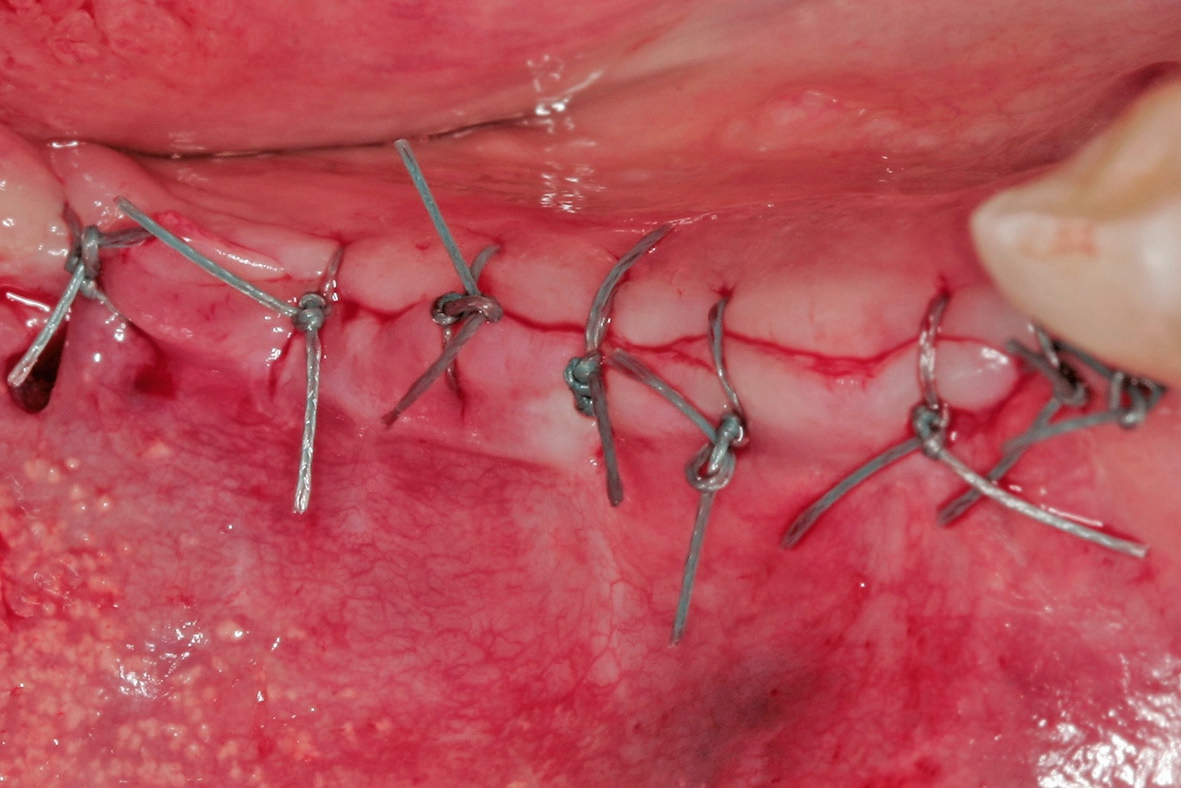

Der Lappen wurde reponiert und mit nicht resorbierbarem Nahtfaden der Stärke 4.0 adaptiert. Um einen spannungsfreien Wundverschluss zu erreichen, wurde apikal eine laterale Matratzennaht gesetzt. Die Nähte wurden nach 14 Tagen entfernt. Nach sechs Monaten komplikationsfreier Wund- und Einheilung kam die Patientin zur Implantatbehandlung erneut in die Praxis (Abb. 6 und 7). Beim Re-Entry wurden die Befestigungsschrauben entfernt, und es wurde eine Knochenkernbiopsie für die histologische Analyse entnommen (Abb. 8 und 9). Die histologische Untersuchung der mit Hämatoxylin-Eosin eingefärbten Schnittpräparate der Probe zeigte den laufenden Umbauprozess des FDBA-Blocks. Die histologische Aufnahme (Abb. 10) zeigte neu gebildeten Geflechtknochen (WB) in engem Kontakt mit dem Allograftmaterial (*) und umgeben von Bindegewebe (CT) und belegte die durch das Allograftmaterial vermittelte Knochenregeneration. Nach Bestimmung der geeigneten Implantatpositionen wurden in regio 47, 46 und 44 drei Bone Level Implantate Straumann® BLX Roxolid® SLActive ® mit einem Durchmesser von 4,5 mm und einer Länge von 10 mm gesetzt (Abb. 11 bis 14). Die Implantate wurden mit RB Verschlusskappen verschlossen, der Wundverschluss erfolgte mit Nahtmaterial der Stärke 4.0 (Abb. 15 und 16).